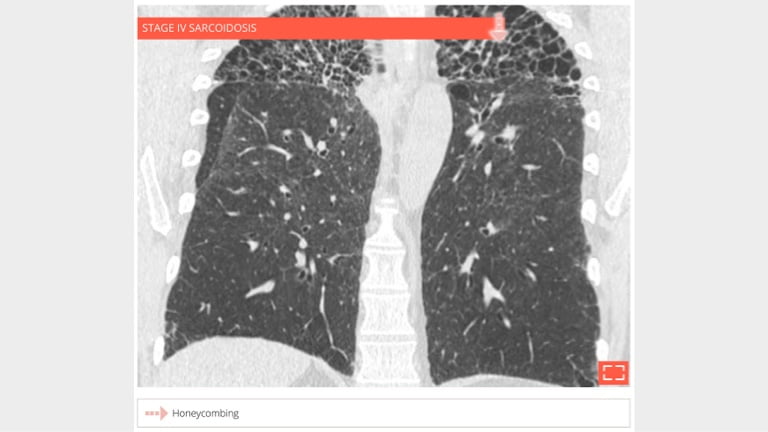

5. Honeycombing

honey-5

• Coronal reformation in the same patient shows the association of honeycombing and reticulation in lung apices.

• Distribution of fibrosis to apices makes this fibrosis incompatible with UIP.